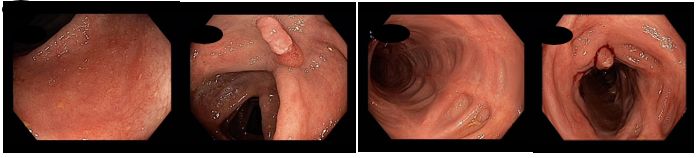

Během pobytu byla pacientka uvedena do klinické remise exklusivní enterální výživou při pokračováním podávání metronidazolu a systémové kortikoterapie s plánem nasazení standardní anti TNF léčby infliximabem nebo adalimumabem po vyřešení administrativních problémů. Během pobytu byla provedena koloskopie s obrazem těžké, segmentální pankolitidy. Z důvodu kolonického postižení podáván mesalazin (v dávce 3,2g/d) a p.o. substituce železem.

Koloskopie 2013/7: Endoskopický obraz těžké, segmentální pankolitidy. Plazivé ulcerace rekta, sigmoidea a descendens. Drobné afty c. transversum a céka. Normální nález v terminálním ileu